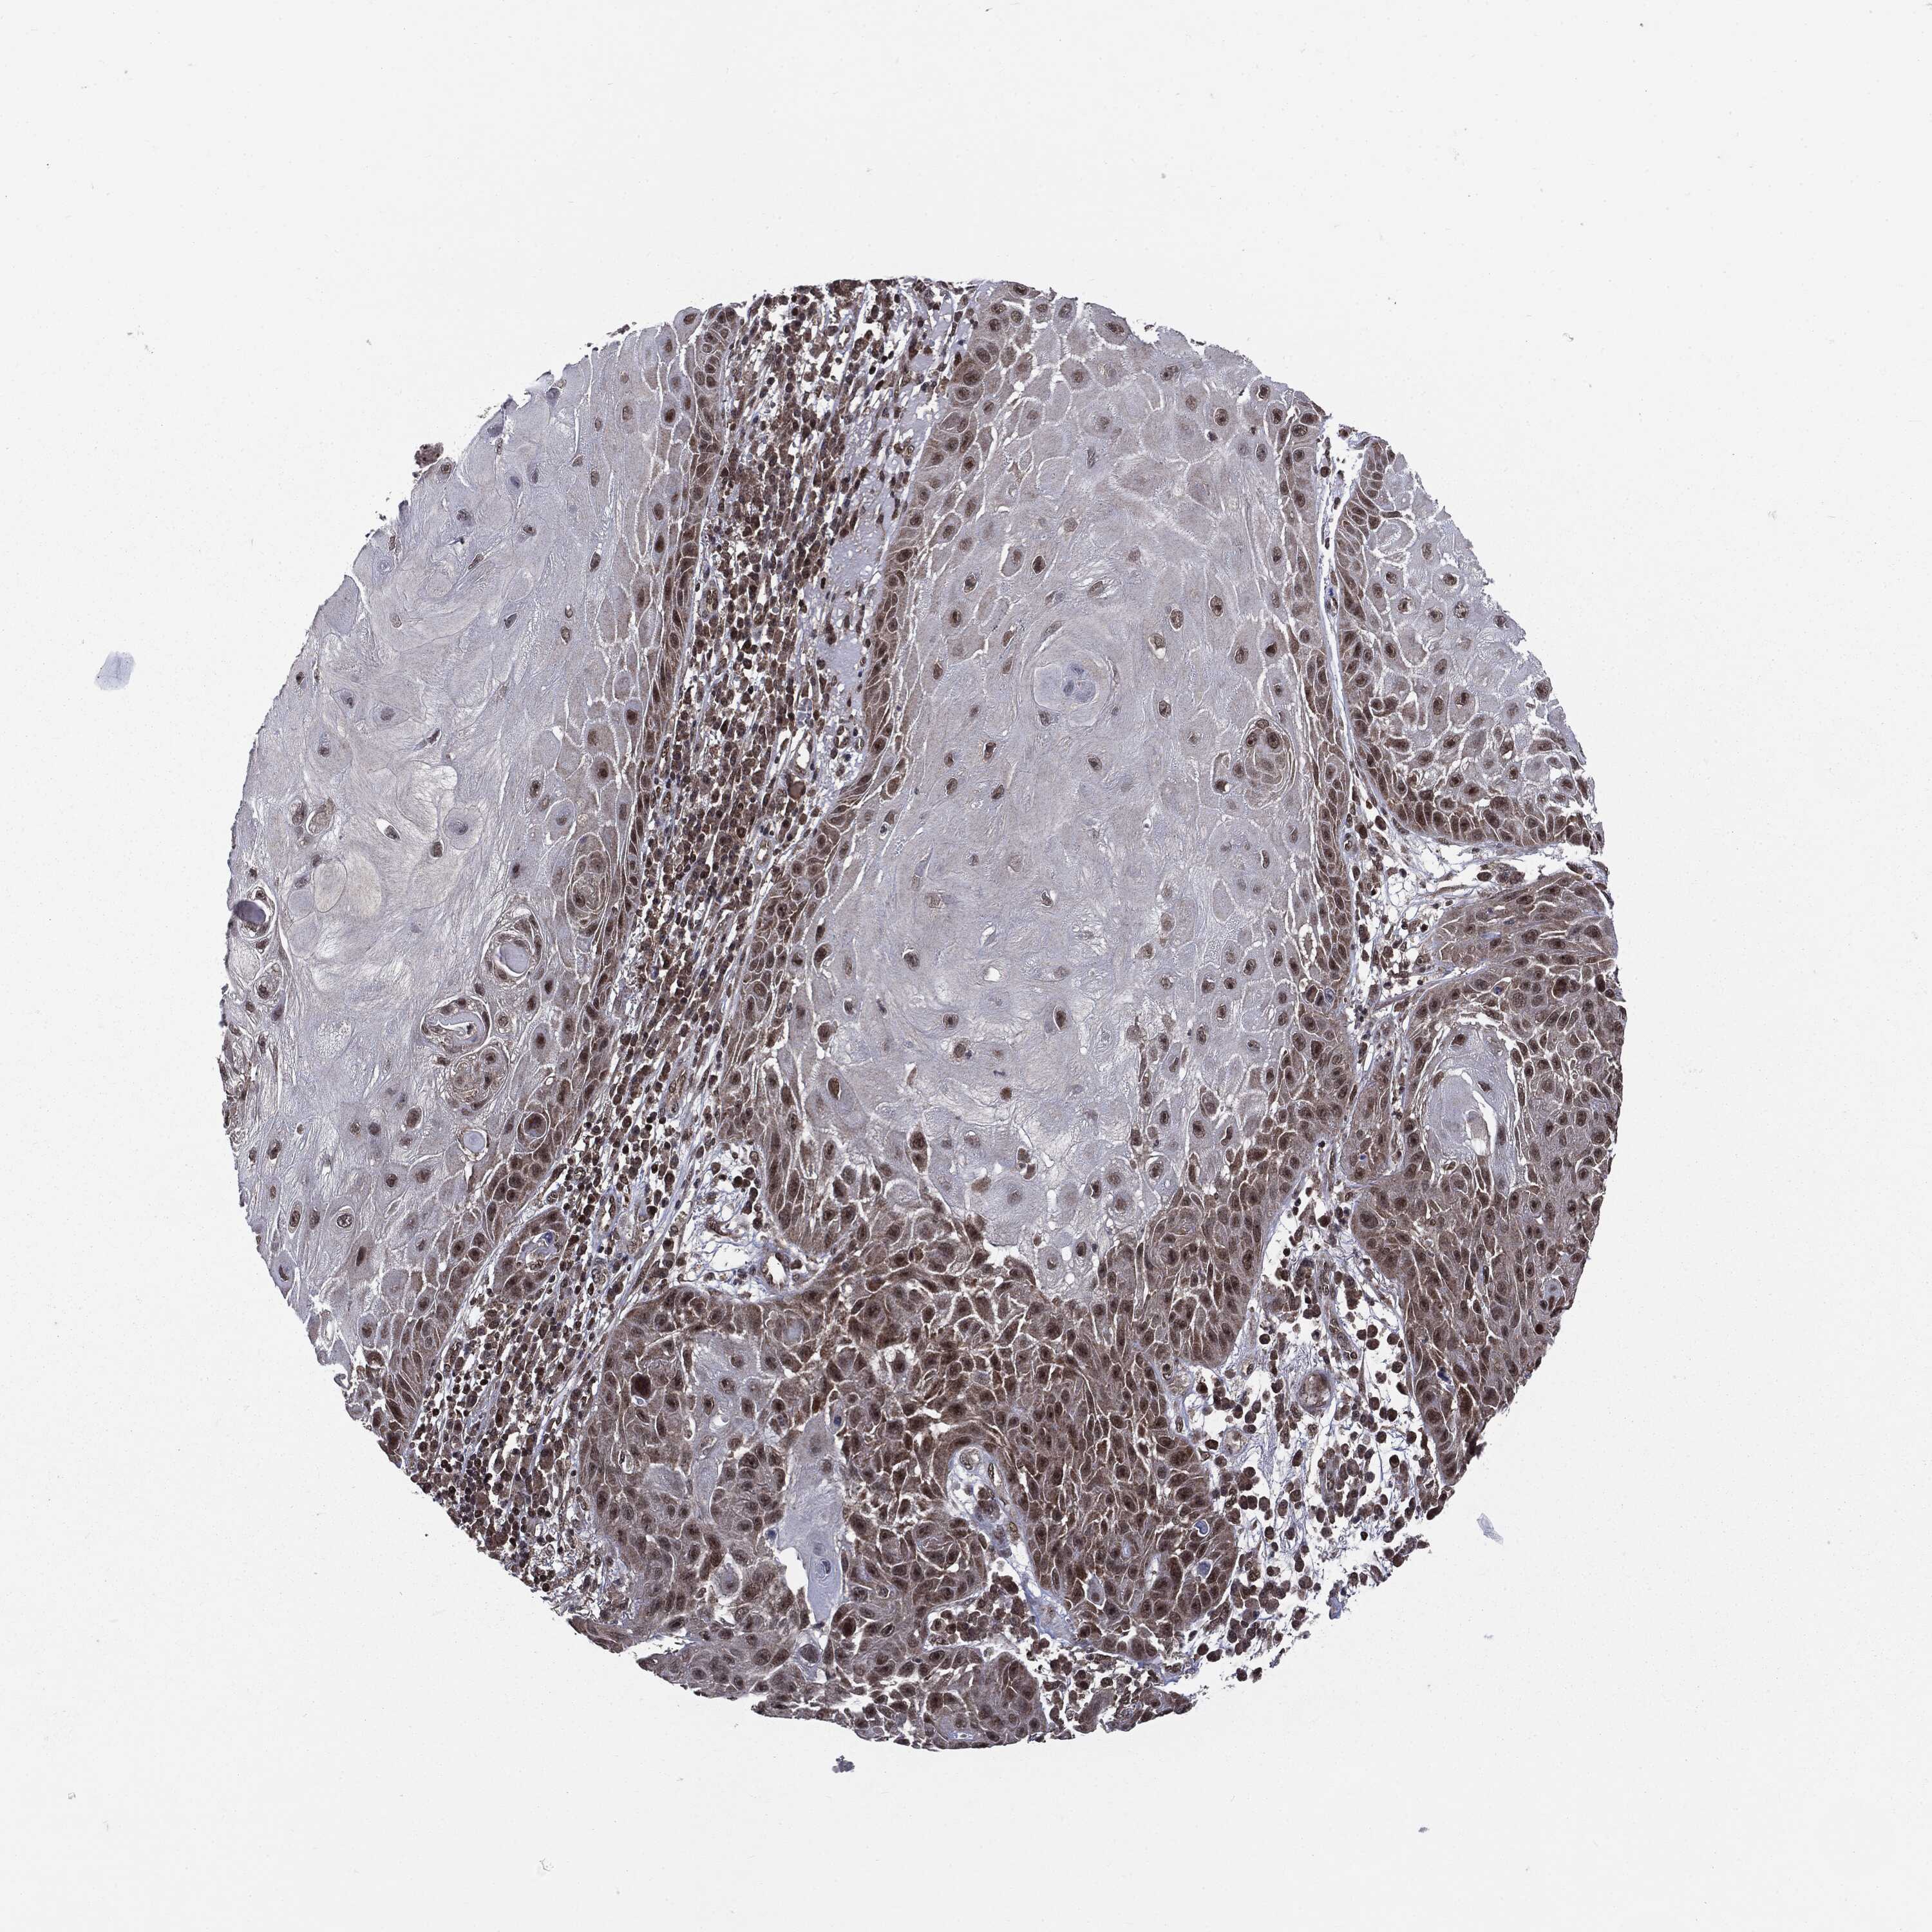

SKIN CANCER - Protein expressioni

A mouse-over function shows sample information and annotation data. Click on an image to view it in a full screen mode. Samples can be filtered based on level of antibody staining by selecting one or several of the following categories: high, medium, low and not detected. The assay and annotation is described here.

Antibody stainingi

Antibody staining in the annotated cell types in the current human tissue is reported as not detected, low, medium, or high, based on conventional immunohistochemistry profiling in selected tissues. This score is based on the combination of the staining intensity and fraction of stained cells.

Each image is clickable and will lead to virtual microscopy that enables deeper exploration of all samples and also displays staining intensity scores, fraction scores and subcellular localization as well as patient and tissue information for each sample.

HPA005695

Staining

High

Medium

Low

Not detected

Intensity

Strong

Moderate

Weak

Negative

Quantity

>75%

75%-25%

<25%

None

Location

Nuclear

Cytoplasmic/membranous

Cytoplasmic/membranous,nuclear

Squamous cell carcinoma, NOS